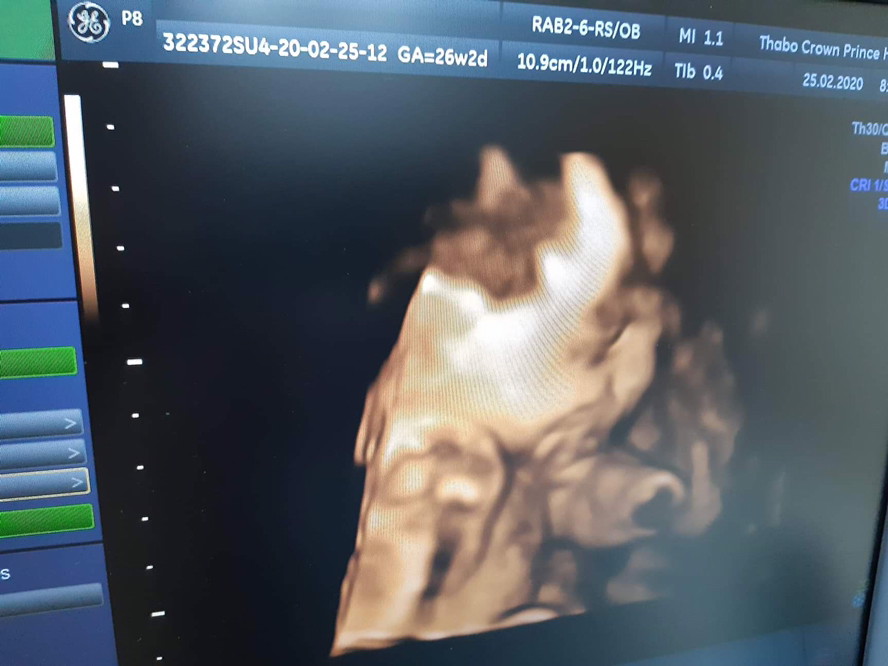

ซาวตอน 26+2 คะ